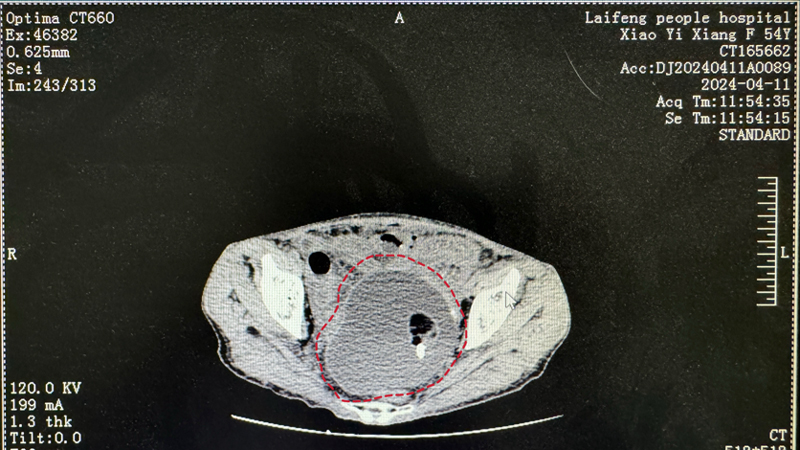

术前的一系列检查结果表明,患者的腹内存在巨大的盆腔包块,可能伴随蒂扭转,需急诊手术探查,而更为严峻的是,她还处于鼻咽癌放化疗期,体形瘦小、体质虚弱,同时还伴有重度贫血和极为严重的低蛋白血症。这样复杂且危险的状况,让整个医疗团队都不禁心弦紧绷。

红色区域内是盆腔巨大包块